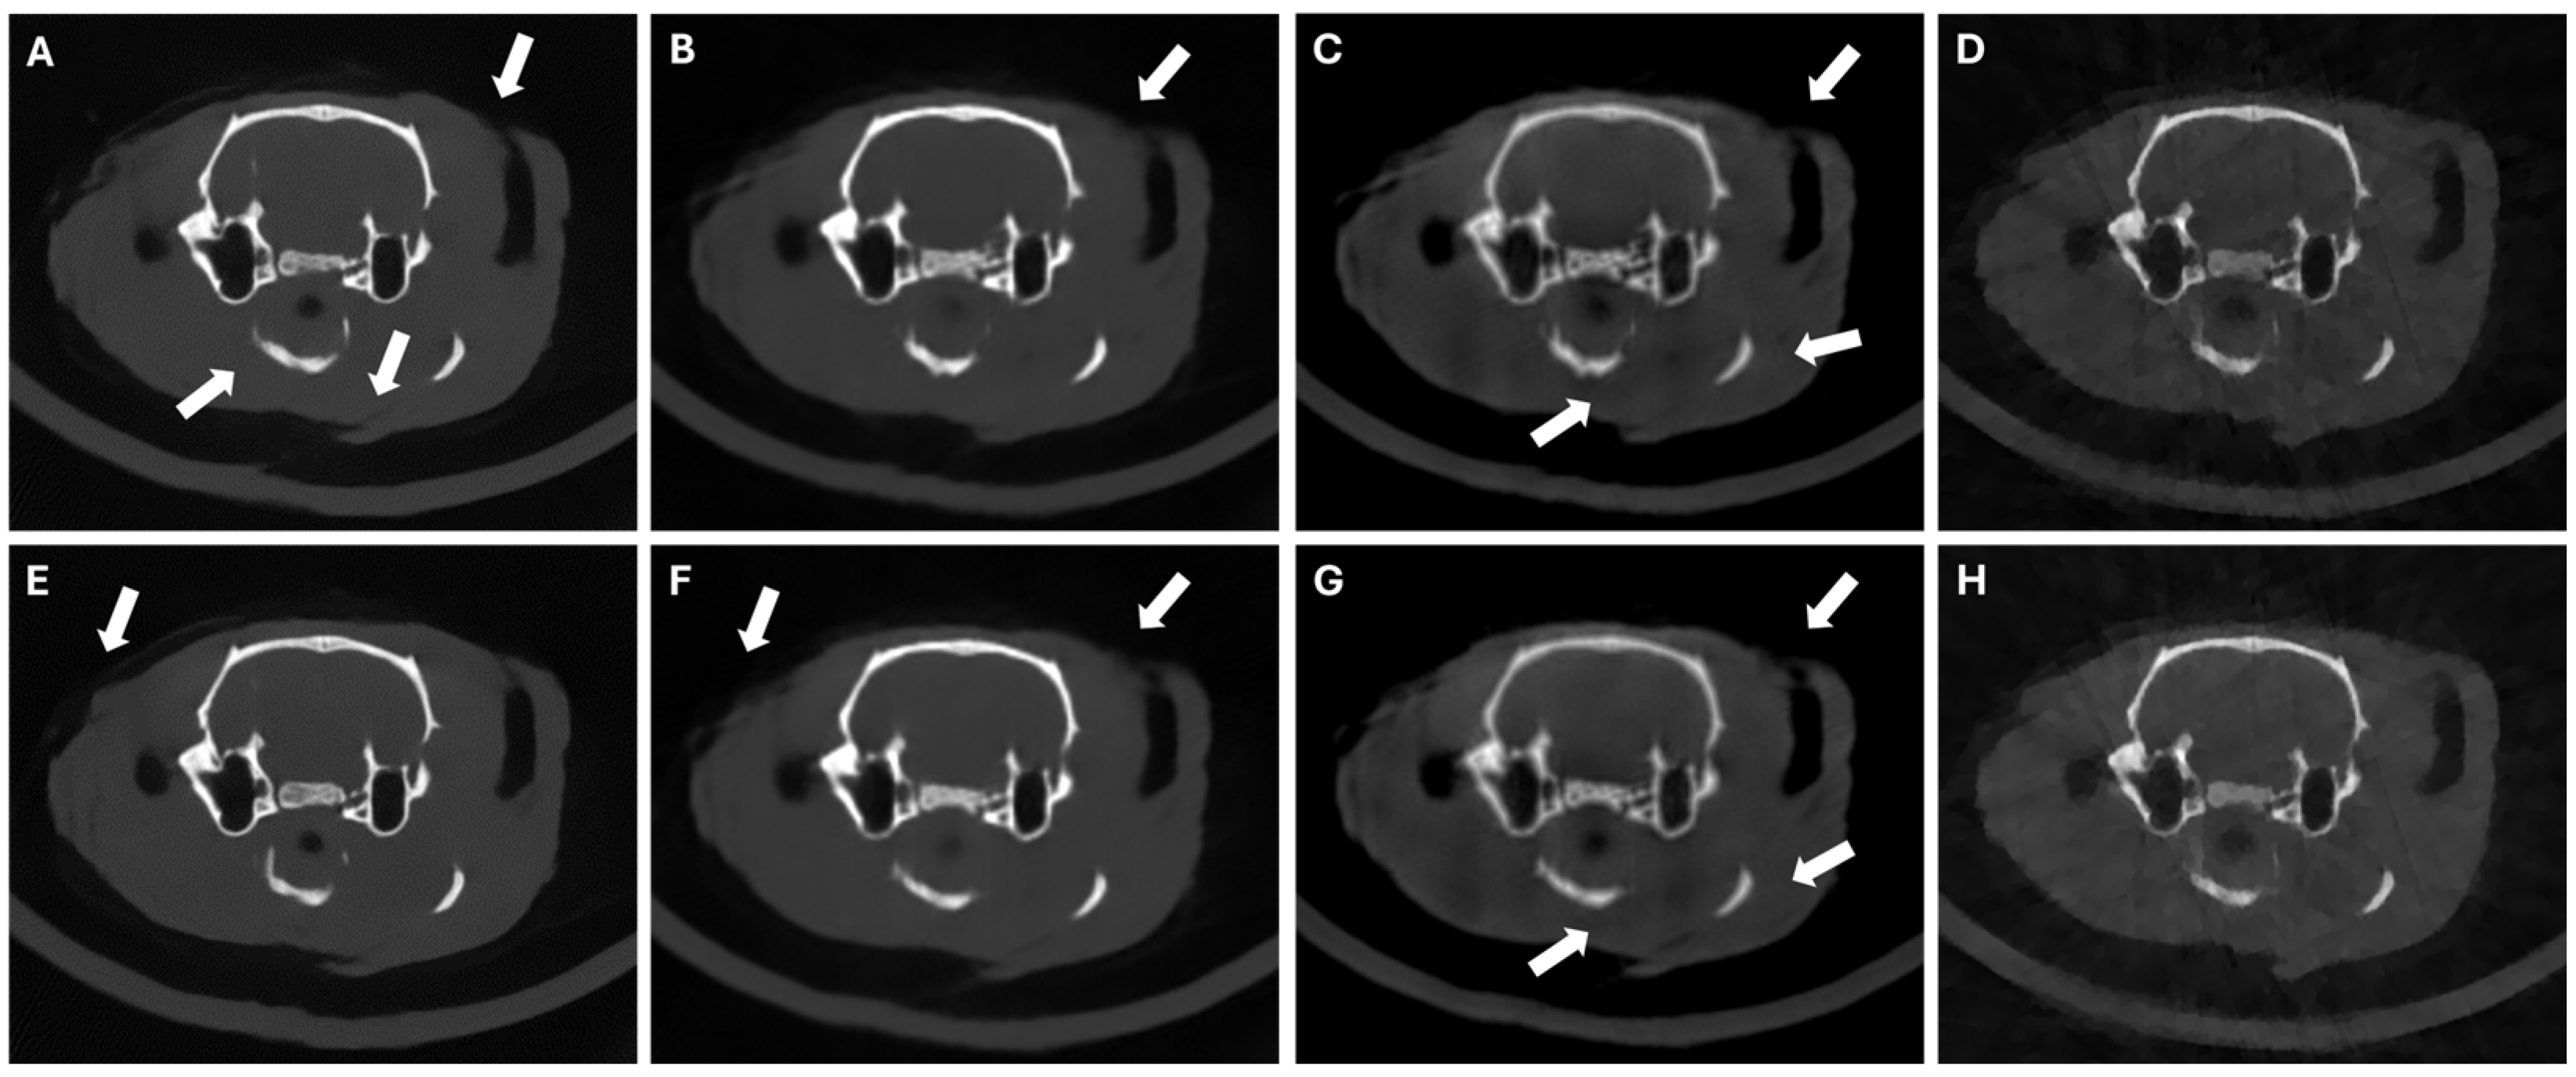

3.3. Results in Conventional Scenarios